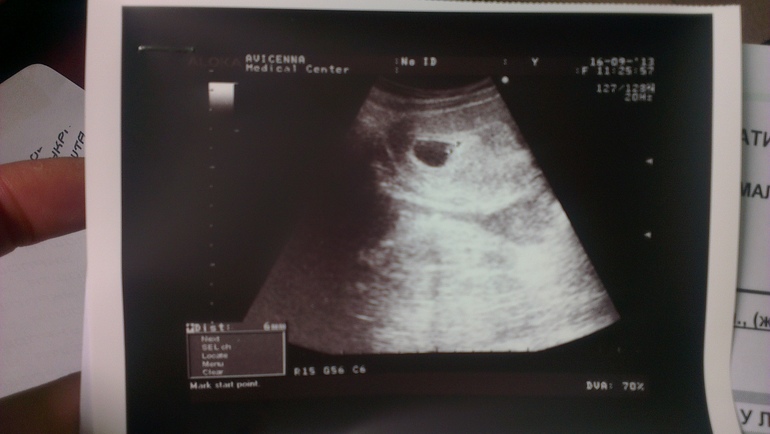

Внематочная Б оказалась не внематочной, лапароскопия, бесконечные анализы и 6 узи и сегодня я даже не услышала а увидела как бъется сердечко моего малышастика!

На 3-4 неделе (на 6й акушерской) после лапароскопи, ооочень опытная узистка заметила в полости матки желточный мешочек а в нем хориончик.

Первая фоточка малыша.

Поздравляю от всего сердца. Здоровья Вам и малышу